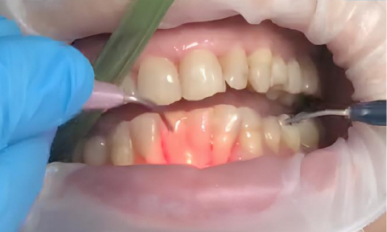

2. Лазерная обработка: Диодный лазер Medency Primo Triplo был настроен на длину волны 635 нм в режиме «периодонтит», с пародонтологической насадкой 400 мкм. Лазерный луч осторожно направляли на воспаленные ткани пародонтальных карманов для удаления бактериального налёта, стимуляции заживления и уменьшения глубины карманов.

Triplo-2.jpg